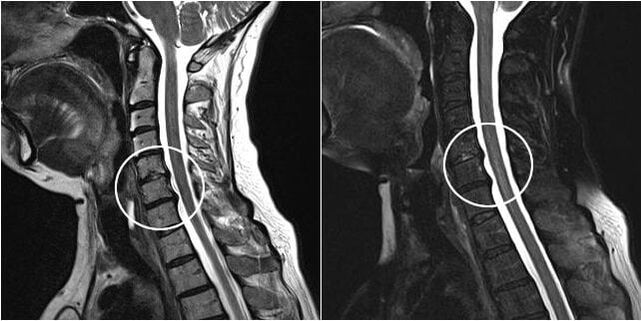

Severe pain in the lower back during pregnancy can sometimes be the cause of a neurological disease (herniated disc or sciatica).

When a disc herniation is detected, the question of surgery arises. This technique involves removing a hernia that compresses the root and creating conditions for its recovery.